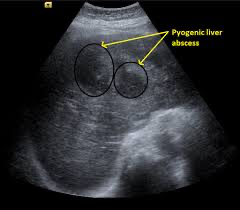

Contributor: Alec Coston, MD Educational Pearls: Hepatic encephalopathy (HE) is defined as a disruption in brain function that results from impaired liver function or portosystemic shunting. Manifests as various neurologic and psychiatric symptoms such as confusion, inattention, and cognitive dysfunction Although ammonia levels have historically been recognized as important criteria for HE, the diagnosis is ultimately made clinically. An elevated ammonia level lacks sensitivity and specificity for HE Trends in ammonia levels do not correlate with disease improvement or resolution A 2020 study published in the American Journal of Gastroenterology evaluated 551 patients diagnosed with hepatic encephalopathy and treated with standard therapy Only 60% of patients had an elevated ammonia level, demonstrating the limitations of ammonia levels However, a normal ammonia level in a patient with concern for HE should raise suspicion for other pathology. In patients with cirrhosis presenting with neuropsychiatric symptoms, consider HE as the diagnosis after excluding other potential causes of altered mental status (i.e., Seizure, infection, intracranial hemorrhage) The primary treatment is lactulose Works by acidifying the gastrointestinal tract. Ammonia (NH₃) is converted into ammonium (NH₄⁺), which is poorly absorbed and subsequently eliminated from the body Also exerts a laxative effect, further enhancing elimination References: Haj M, Rockey DC. Ammonia Levels Do Not Guide Clinical Management of Patients With Hepatic Encephalopathy Caused by Cirrhosis. Am J Gastroenterol. 2020 May;115(5):723-728. doi: 10.14309/ajg.0000000000000343. PMID: 31658104.\ Lee F, Frederick RT. Hepatic Encephalopathy-A Guide to Laboratory Testing. Clin Liver Dis. 2024 May;28(2):225-236. doi: 10.1016/j.cld.2024.01.003. Epub 2024 Jan 30. PMID: 38548435. Vilstrup, Hendrik1; Amodio, Piero2; Bajaj, Jasmohan3,4; Cordoba, Juan1,5; Ferenci, Peter6; Mullen, Kevin D.7; Weissenborn, Karin8; Wong, Philip9. Hepatic encephalopathy in chronic liver disease: 2014 Practice Guideline by the American Association for the Study Of Liver Diseases and the European Association for the Study of the Liver. Hepatology 60(2):p 715-735, August 2014. | DOI: 10.1002/hep.27210 Weissenborn K. Hepatic Encephalopathy: Definition, Clinical Grading and Diagnostic Principles. Drugs. 2019 Feb;79(Suppl 1):5-9. doi: 10.1007/s40265-018-1018-z. PMID: 30706420; PMCID: PMC6416238. Summarized by Ashley Lyons, OMS3 | Edited by Ashley Lyons & Jorge Chalit, OMS4 Get your tickets to Tox Talks Event, Sept 11, 2025: https://emergencymedicalminute.org/events-2/ Donate: https://emergencymedicalminute.org/donate/